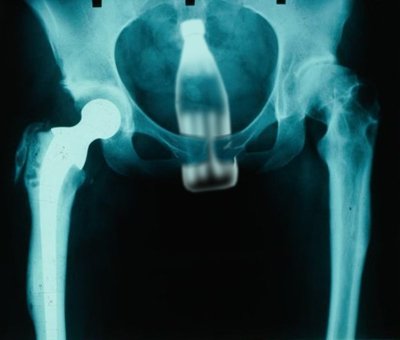

While I'd like to admit to using Coke bottles (merely for the fact that I'm psuedo-shitting on American consumerism), it's usually my faithful shampoo/conditioner bottle that I experiment with

And the aftermath?

YOU do the math.

Pete, how could you???